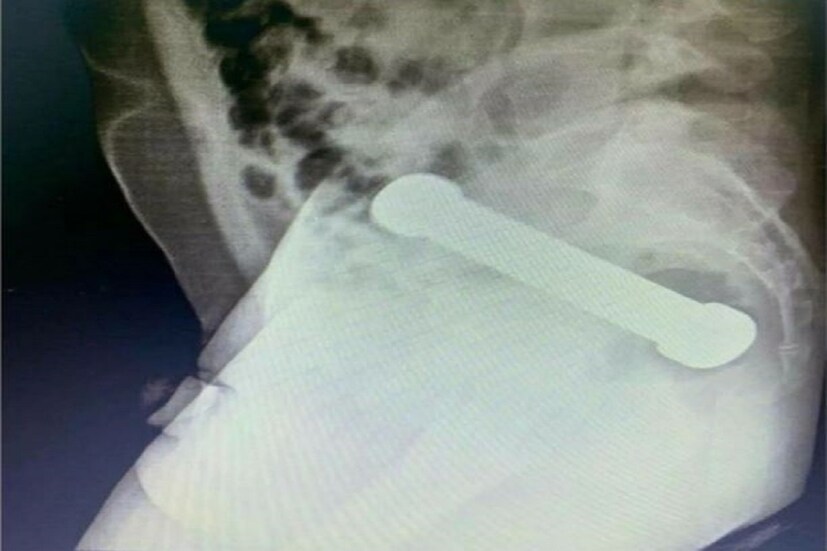

ইন্টারন্যাশানাল জার্নাল অফ সার্জারি কেস রিপোর্টে প্রকাশিত খবরে এই বিষয়টি সামনে এসেছে৷ ব্রাজিলের মুআউসের বাসিন্দা এক ব্যক্তির পেট ব্যাথা হয়৷ তারপর তাঁকে হাসপাতালে পাঠানো হয়৷ যেখানে চিকিৎসকরা তাঁর এক্সরে করানোর সিদ্ধান্ত নেন৷ সেখানে সেই বক্তি প্রচপর নাটক করে৷ ওই ব্যক্তি এক্সরে করানোর জন্য প্রস্তুত ছিল না৷ যদিও চিকিৎসকরা রিপোর্ট দেখে অবাক হয়ে যায়৷ ওই ব্যক্তির মলাশয়ে ২ কিলোর ডাম্বেল ঢুকেছিল৷

আন্তর্জাতিক জার্নাল অফ সার্জারি কেস রিপোর্টস অনুযায়ি এনা এলিসা ডি লন্ডা এয়র তাঁর দল বলেন প্রথমে তাঁরা ভেবেছিলেন টুইজার্সের সাহায্যে তা বার করে নেওয়া হবে৷ কিন্তু ডাম্বেল এতটাই ভারি ছিল যে তা এভাবে বার করা যায়নি৷ এরপর তাঁরা খুব ভয়ানক ভাবে ওই ডাম্বেলটা বার করে আনেন৷ ডাক্তাররা মলাশয়ে নিজের হাত ঢুকিয়ে মলাশয় থেকে বার করে আনেন৷